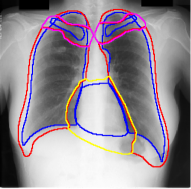

A few existing segmentation label noise approaches (Zhu et al., 2019; Zhang et al., 2020b; a) directly apply methods in classification label noise. However, these methods assume the label noise for each pixel is i.i.d. (independent and identically distributed). This assumption is not realistic in the segmentation context, where annotation is often done by brushes, and error is usually introduced near the boundary of objects. Regions further away from the boundary are less likely to be mislabeled (see Fig. 1(c) for an illustration). Therefore, in segmentation tasks, label noise of pixels has to be spatially correlated. An i.i.d. label noise will result in unrealistic annotations as in Fig. 1(b).

We propose a novel label noise model for segmentation annotations. Our model simulates the real annotation scenario, where an annotator uses a brush to delineate the boundary of an object. The noisy boundary can be considered a random yet continuous distortion of the true boundary. To capture this noise behavior, we propose a Markov process model. At each step of the process, two Bernoulli variables are used to control the expansion/shrinkage decision and the spatial-dependent expansion/shrinkage strength along the boundary. This model ensures the noisy label is a continuous distortion of the ground truth label along the boundary, as shown in Fig. 1(c). Our model also includes a random flipping noise, which allows random (yet sparse) mislabels to appear even at regions far away from the boundary.

For each of these three datasets, we use three noise settings, denoted by , and . and are two settings synthesized by our Markov process with (expansion) and (shrinkage), respectively. Figure 4 shows examples of our synthesized label noise. We also include the mix of random dilation and erosion noise used by previous work (Zhu et al., 2019; Zhang et al., 2020b; a). This is achieved by randomly dilate or erode a mask with a number of pixels. Note that our Markov label noise can theoretically include this type of noise by setting . Detailed parameters for these settings are provided in the Appendix.